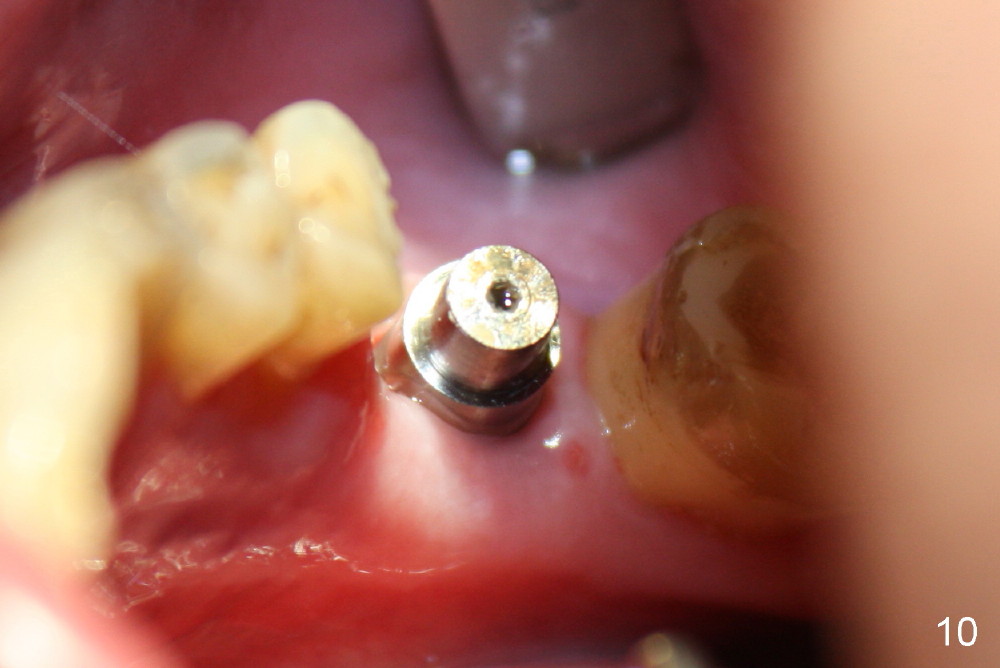

When the perio dressing is removed in office 24 days postop (Fig.9), the rough surface of the implant (R) is exposed buccally.  Normally the smooth surface should contact the gingiva (S).   Lingually implant/gingiva position is within normal limit (Fig.10).  The patient returns for restoration 4 months postop (Fig.11,12).  There is bone formation in the mesial socket and new bone appears to have grown toward the implant (Fig.11 <).  A straight abutment appears to be in the middle of the edentulous space (Fig.12 A).   But it is difficult to seat the crown.  Three months post cementation, the patient complains of food impaction mesially (Fig.10 ^), although bone density continues to increase in the mesial socket and there is no mesial coronal thread exposure (*).  Retrospectively the implant should be tried to be placed in the septum as much as possible to have a favorable restorative axis (Fig.14).  The crown is re-fabricated with larger mesial contact area.  It is temporarily cemented because of slightly loose distal contact (Fig.15).  A few days later, the patient requests permanent cementation, because although the distal contact is loose, it is easy to remove food.  Mesial food impaction is less likely, but it is more difficult to be removed.